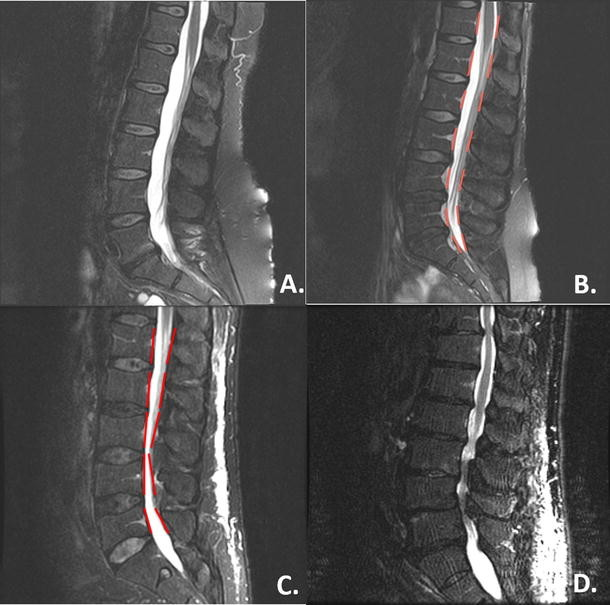

آزمایشهای تصویربرداری: تکنیکهایی مانند اشعه ایکس (X-rays)، امآرآی (MRI) یا سیتیاسکن (CT scans) برای مشاهده ستون فقرات و شناسایی نواحی باریکشده.